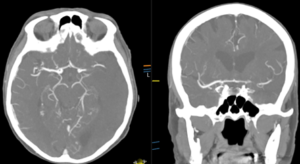

Occlusion (blood clot) on CT Angiogram